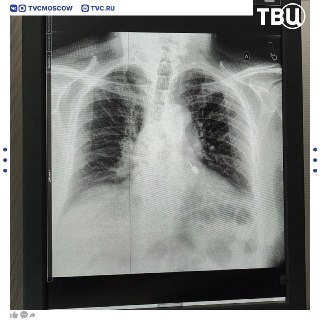

😱 82-летний пенсионер вдохнул стоматологический бур во время лечения зубов

Его экстренно прооперировали в Мытищинской областной клинической больнице и спустя несколько дней отпустили домой.